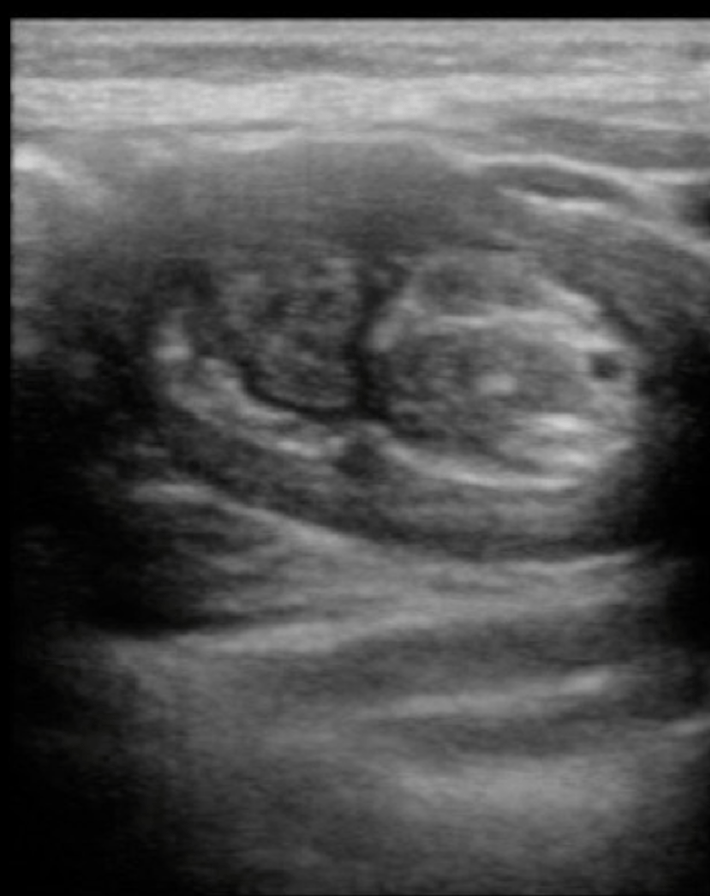

What are the ultrasound findings of intussusception?

- “Target” or “bulls-eye” lesion caused by layers of intestine within intestine. Colour duplex imaging can be used to detect development of ischemia.

- Below are still U/S images kindly contributed by Dr. Mark Tessaro. The first image is the typical “target/donut” lesion, the bottom left image is the oblique- “pseudokidney”, and the bottom right is the longitudinal “sandwich” view.